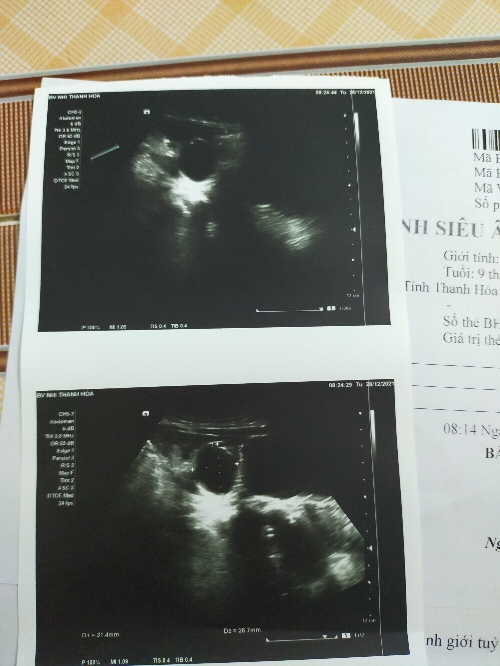

Chào bác sĩ, bé nhà e được 9 thang, e cho bé đi khám ở bệnh viện nhi thanh hoá biết bé có nang ở mạn sườn bên phải, mấy hôm vừa rồi bé có nôn, có lúc nôn cả ra dịch màu nâu thâm, bé bú ít, ăn ít. Mỗi lần nôn bé mệt lã người chỉ nằm ngủ ko chơi ko đùa. Mong các sĩ tư vấn giúp gia đình với ạ.

Với nang dịch kích thước 3cm cũng tương đối lớn. Tuy nhiên nang dịch này bản chất là dịch gì? Có phải u máu không? Có gây ra các triệu chứng tiêu hoá nôn; ăn kém ko thì bs cần hỏi em thêm một số triệu chứng nữa. Nếu có thời gian em đặt lịch khám bs để trao đổi trực tiếp nhé. Đặt lịch đơn giản lắm